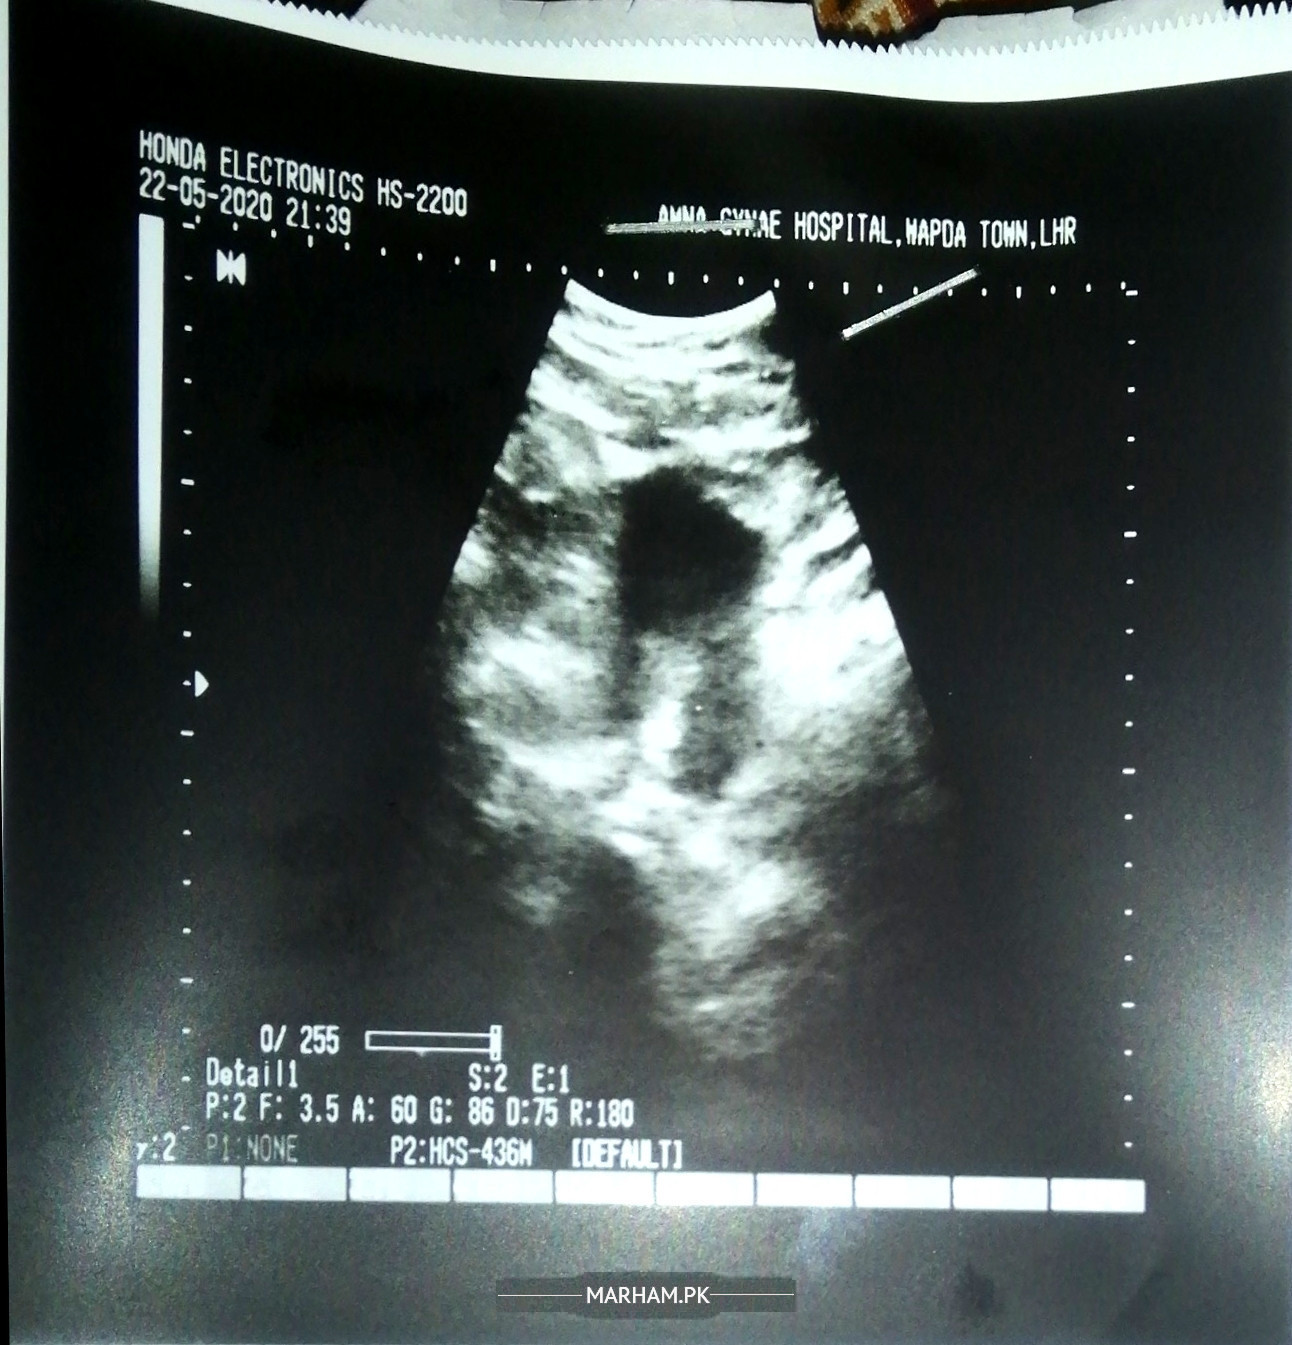

Ultrasound of last night

Thanks for the reply. Please check the attached ultrasound of 2nd day of menstrual cycle, what does it show? And what blood tests are needed in general for this condition?